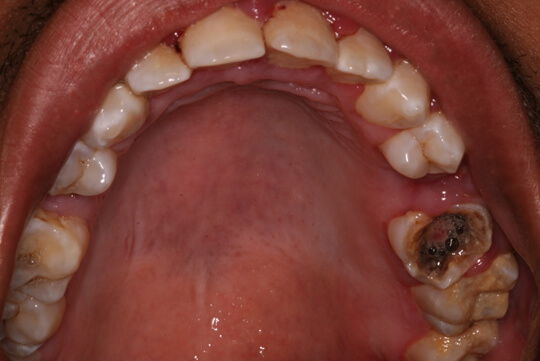

| Răng hàm bị sâu |

Khi bị sâu răng, trên răng sẽ xuất hiện các lỗ đen nhỏ. Lỗ đen này sẽ rộng và sâu dần. Khác với sâu răng cửa thường xuất hiện ở cạnh cắn hai bên, đối với sâu răng hàm, thường bị sâu ở các rãnh trên mặt nhai trước sau đó là sâu ở rãnh mặt bên. Vì răng hàm thường có nhiều gờ rãnh hơn các răng mặt.

Do đó, nếu răng hàm bị sâu thì mặt rãnh mặt nhai sẽ đen trước tiên, sau đó vết sâu lan rộng, vỡ ra thành miếng lớn. Cũng có trường hợp các lỗ sâu này hình thành ở thân răng và tiến dần vào bên trong ngà răng và cuối cùng là tủy răng.